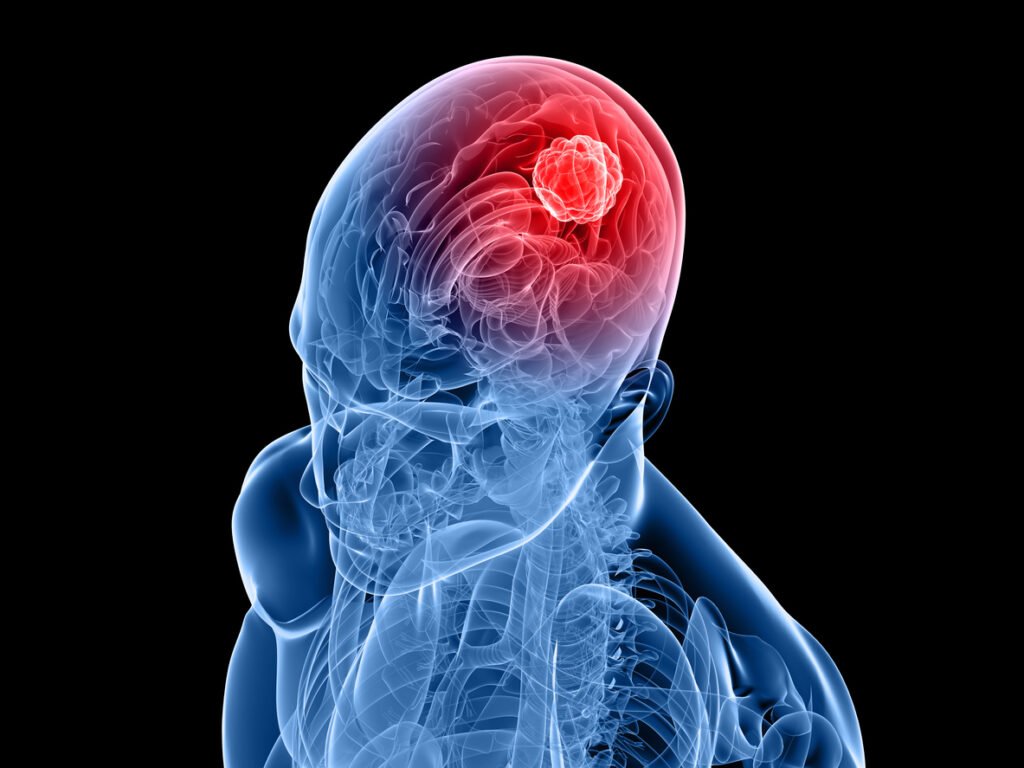

ಮೆದುಳಿನಲ್ಲಿ ಗಡ್ಡೆಗಳು ಬೆಳೆಯುವುದು ಅಂದರೆ ಬ್ರೈನ್ ಟ್ಯೂಮರ್ ಎನ್ನುವುದು ಬಹಳ ಗಂಭೀರವಾದಂತಹ ಕಾಯಿಲೆಯಾಗಿದೆ. ಚಿಕಿತ್ಸೆಯನ್ನು ವಿಳಂಬ ಮಾಡಿದಷ್ಟು ಇದರಿಂದ ಉಂಟಾಗುವ ತೊಂದರೆಗಳು ಹೆಚ್ಚಾಗಬಹುದು. ಒಬ್ಬ ವ್ಯಕ್ತಿಯಲ್ಲಿ ಮೆದುಳಿನ ಗಡ್ಡೆಯಾದಾಗ ರಾತ್ರಿ ಸಮಯದಲ್ಲಿ ಕೆಲವು ಲಕ್ಷಣಗಳು ಕಂಡುಬರುತ್ತವೆ ಎಂದು ತಜ್ಞರು ಹೇಳುತ್ತಾರೆ. ಈ ಲಕ್ಷಣಗಳನ್ನು ನಿರ್ಲಕ್ಷಿಸದಿದ್ದರೆ ಬ್ರೈನ್ ಟ್ಯೂಮರ್ ನಿಂದ ಪರಿಹಾರ ಕಂಡುಕೊಳ್ಳಬಹುದು.

ಸಾಮಾನ್ಯವಾಗಿ ಮೆದುಳಿನಲ್ಲಿನ ಜೀವಕೋಶಗಳು ಇದ್ದಕ್ಕಿದ್ದಂತೆ ಬೆಳೆಯಲು ಪ್ರಾರಂಭಿಸಿದಾಗ ಮೆದುಳಿನ ಗಡ್ಡೆ ಉಂಟಾಗುತ್ತದೆ. ಹಾನಿಕರವಲ್ಲದ ಗೆಡ್ಡೆಗಳು ಕ್ಯಾನ್ಸರ್ ಅಲ್ಲ, ಆದರೆ ಅವು ನಿಧಾನವಾಗಿ ಬೆಳೆಯುತ್ತವೆ. ಮತ್ತೊಂದೆಡೆ, ಮಾರಕ ಗಡ್ಡೆಗಳು ವೇಗವಾಗಿ ಬೆಳೆಯುತ್ತವೆ ಮಾತ್ರವಲ್ಲ ಇದು ಜೀವಕ್ಕೆ ಅಪಾಯಕಾರಿಯಾಗಬಹುದು. ಚಿಕಿತ್ಸೆಯು ಗಡ್ಡೆಯ ಲಕ್ಷಣಗಳು, ಅದು ಎಲ್ಲಿದೆ, ಅದರ ಗಾತ್ರ ಮತ್ತು ಅದು ಕ್ಯಾನ್ಸರ್ ಆಗಿದೆಯೇ ಅಥವಾ ಇಲ್ಲವೇ ಎಂಬುದರ ಮೇಲೆ ಅವಲಂಬಿತವಾಗಿರುತ್ತದೆ ಎಂದು ತಜ್ಞರು ಹೇಳುತ್ತಾರೆ.